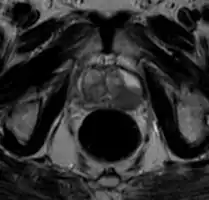

MRI Organ-confined prostate cancer

On MRI, the central and transitional zones both have lower T2 signal than the peripheral zone. Since the central and transitional zones cannot be distinguished from each other, they can be best described as the central gland on MRI. Thus, the peripheral gland has a higher signal on T2WI than the central gland. In the peripheral gland, prostate cancer appears as a low-intensity lesion. However, in the central gland, low-intensity lesions cannot be distinguished from the low-intensity central gland. Diffusion restriction is instrumental in identifying and characterizing central gland lesions. Lymphadenopathy can be seen best on postcontrast, fat-suppressed T1WI.

Other regions can be described on MRI. The anterior fibromuscular stroma and the prostate capsule along the posterior and lateral prostate have a low T2WI signal, in contrast with the bright signal of the peripheral zone. Extraprostatic extension can be seen with disruption of capsule integrity.